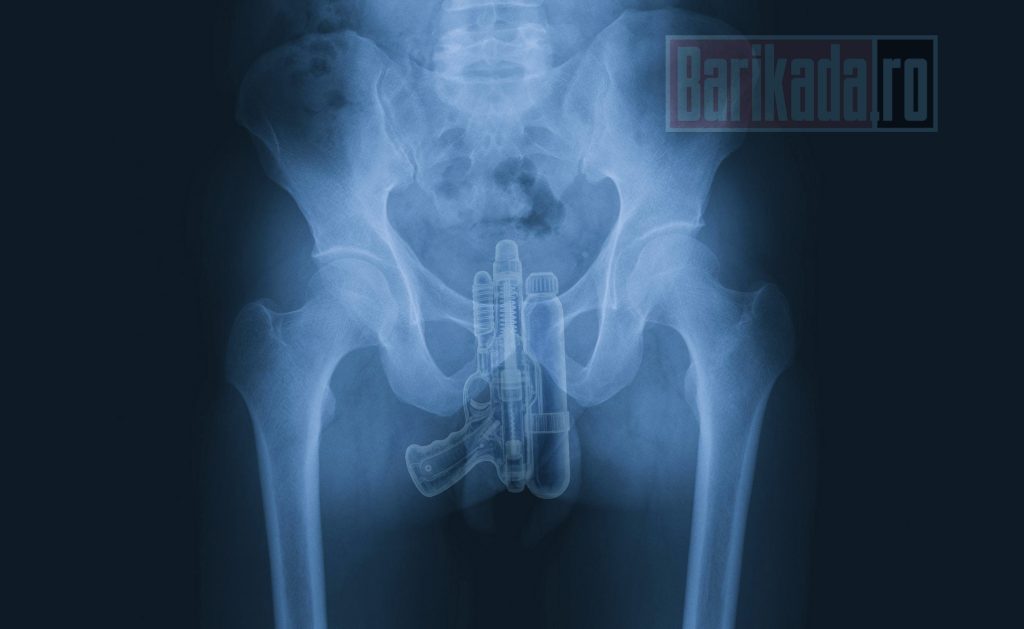

Primul caz: pistol cu vacuum, extras chirurgical

Primul pacient, angajat MAI, a ajuns la UPU acuzând dureri intense și disconfort major. Investigațiile imagistice au relevat prezența unui obiect străin: un pistol de jucărie cu sistem de vacuum, similar celor utilizate în jocurile cu apă pentru copii.

Sursele noastre susțin că obiectul fusese absorbit profund pe cale rectală, iar extragerea nu a fost posibilă prin manevre simple. Medicii au fost nevoiți să recurgă la o intervenție chirurgicală pentru a evita complicații precum perforația intestinală sau hemoragia internă. Operațiunea s-a dovedit dificilă, din cauza formei și mecanismului jucăriei. Pacientul a fost stabilizat postoperator și monitorizat.